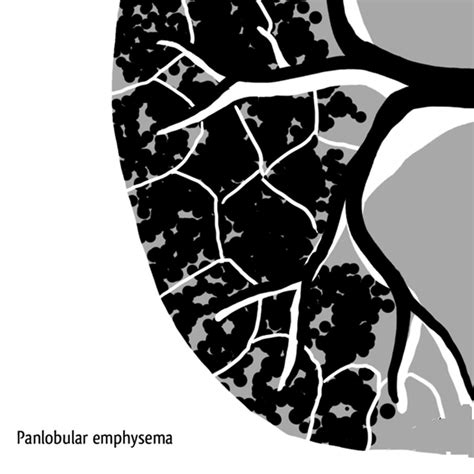

• 4 types of emphysema